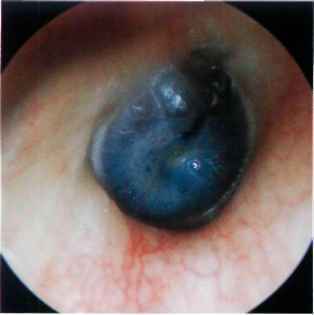

Question 2

Question

Describe this image:

Answer

Blue tympanic membrane

Due to blood behind the eardrum

Not a serious complication of acute otitis media

Perforation is seen